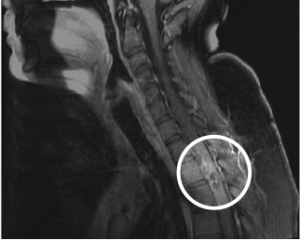

Figure 2: Thoracic MRI showing areas of hemorrhage in the spinal cord most prominent at the T2–T3 level, with multiple serpentine structures, most in keeping with a spinal cord vascular malformation such as an sAVM.